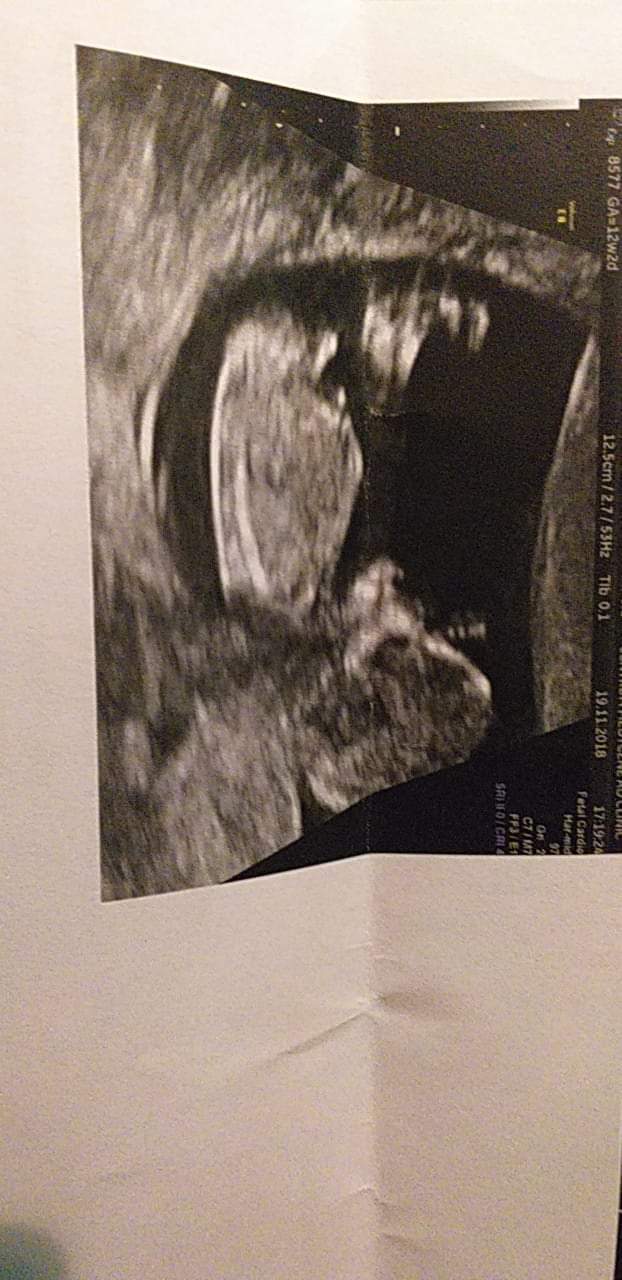

Ja po prenatalnych. Wszystko jest dobrze na obecną chwilę, ryzyko chorób genetycznych niskie. Termin porodu się zmienił na 28 maja, crl 6,5 cm i na 80 % będzie kolejny syn xD jestem skazana na samych chłopców :) zdjęcia mam ale głównie głowy, serca i kończyn, jedyne sensowne zaraz wam wrzucę Zobacz załącznik 917882